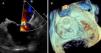

Figure 3.

Follow-up TEE. Color Doppler 2D TEE (A) and 3D TEE (B) showing complete obliteration of LAA with no residual leak.